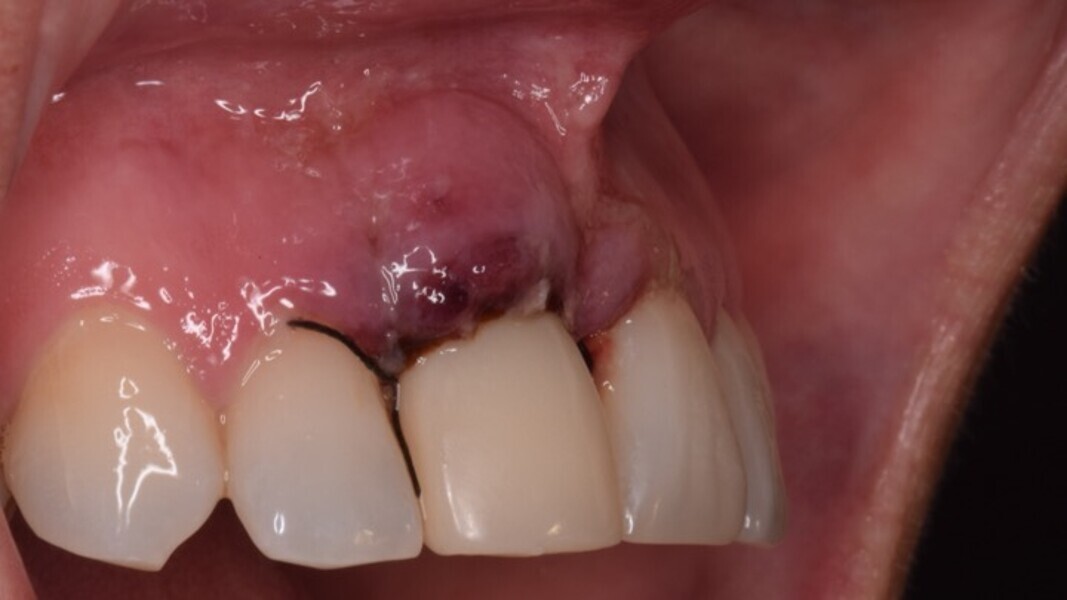

Figura 5. Hundimiento de la zona estética anterior inmediatamente después de la extracción del diente por la reabsorción de la pared vestibular.